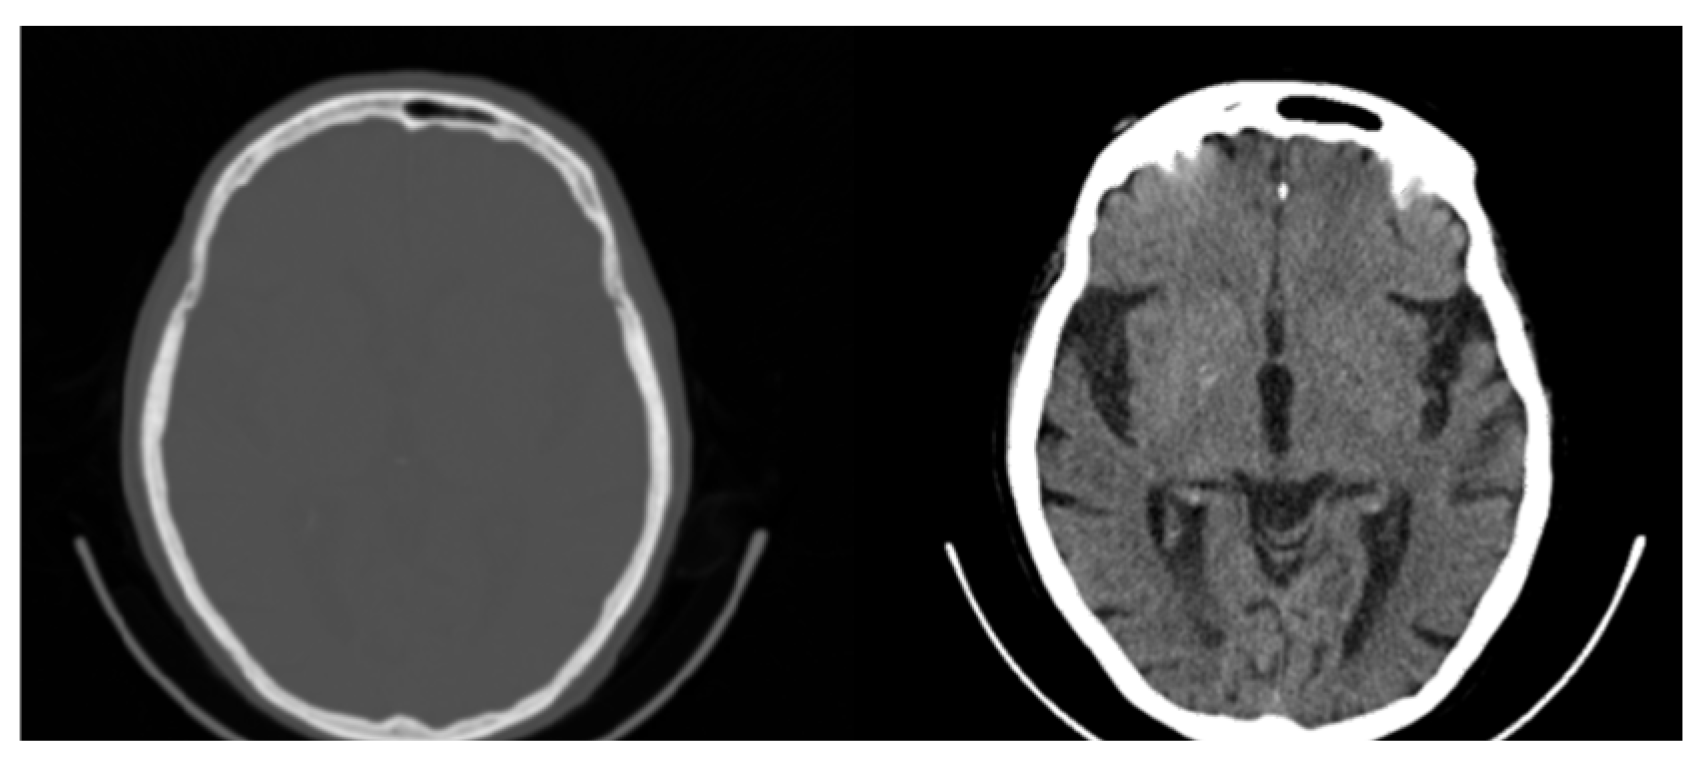

3.1. CIT Application

3.2. Colormap Folding Application